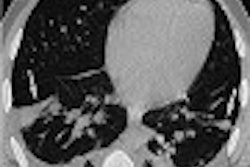

Over the past several years, a number of studies have shown that software-based coregistration of PET and CT images is more accurate than CT alone, especially for detecting non-small cell lung cancers and mediastinal lymph node metastases, the authors wrote in Radiology Online (September 19, 2002).

PET images were first analyzed alone, then fused with CT images acquired at increasingly higher mA settings: 10, 40, 80 and 120 mA. Staging was also performed in an effort to assess the clinical effect of PET-CT examinations.

PET combined with 10-mA CT defined 135 lesions as tumors, 50 as inflammation, and 54, other. Compared with the reference standard, 133 lesions were TP, 109 TN, and 5 FN, the authors wrote. Compared with the reference standard, low-dose combined technique yielded sensitivity of 96% and specificity of 99%.

Adding 10-mA CT to PET increased the percentage of correct diagnoses from 72% to 90%, the authors wrote. But raising the mA to 40 or 80 increased correct diagnoses just two percentage points, to 92%. Increasing the voltage to 120 mA did not affect the results.